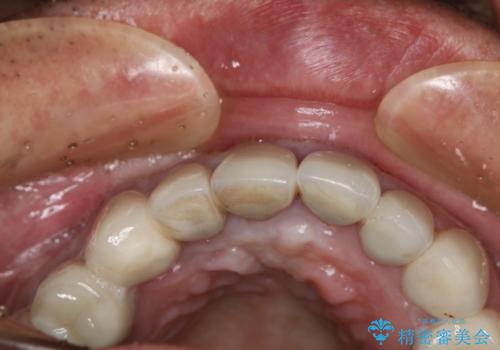

- 事故による外傷で前歯に歯根が真っ二つに折れてしまい、保存不可能となってしまった部分にインプラント治療を計画しました。

近年、インプラントの素材や手術法の研究が進み、保存不可能となった歯牙に対して抜歯してすぐインプラントを埋入し、さらに直後から仮歯がを入れ噛むことができる【抜歯即時埋入】【即時荷重】という技法が確立されました。